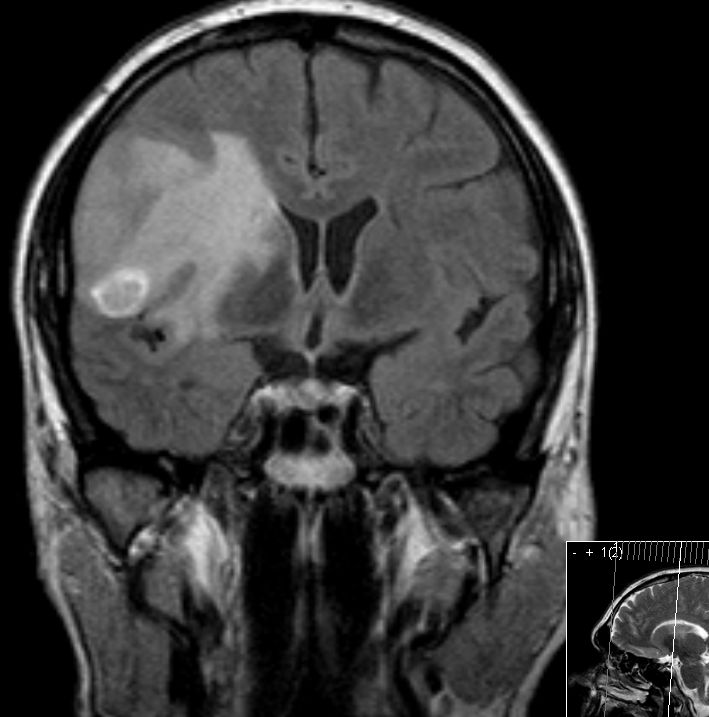

Hirnmetastasen |

52-jähriger Mann mit ossär und visceral

metastasiertem Nierenzellkarzinom. Jetzt Metastase rechts temporal mit

ausgedehnten Hirnödem.![]() | ||||